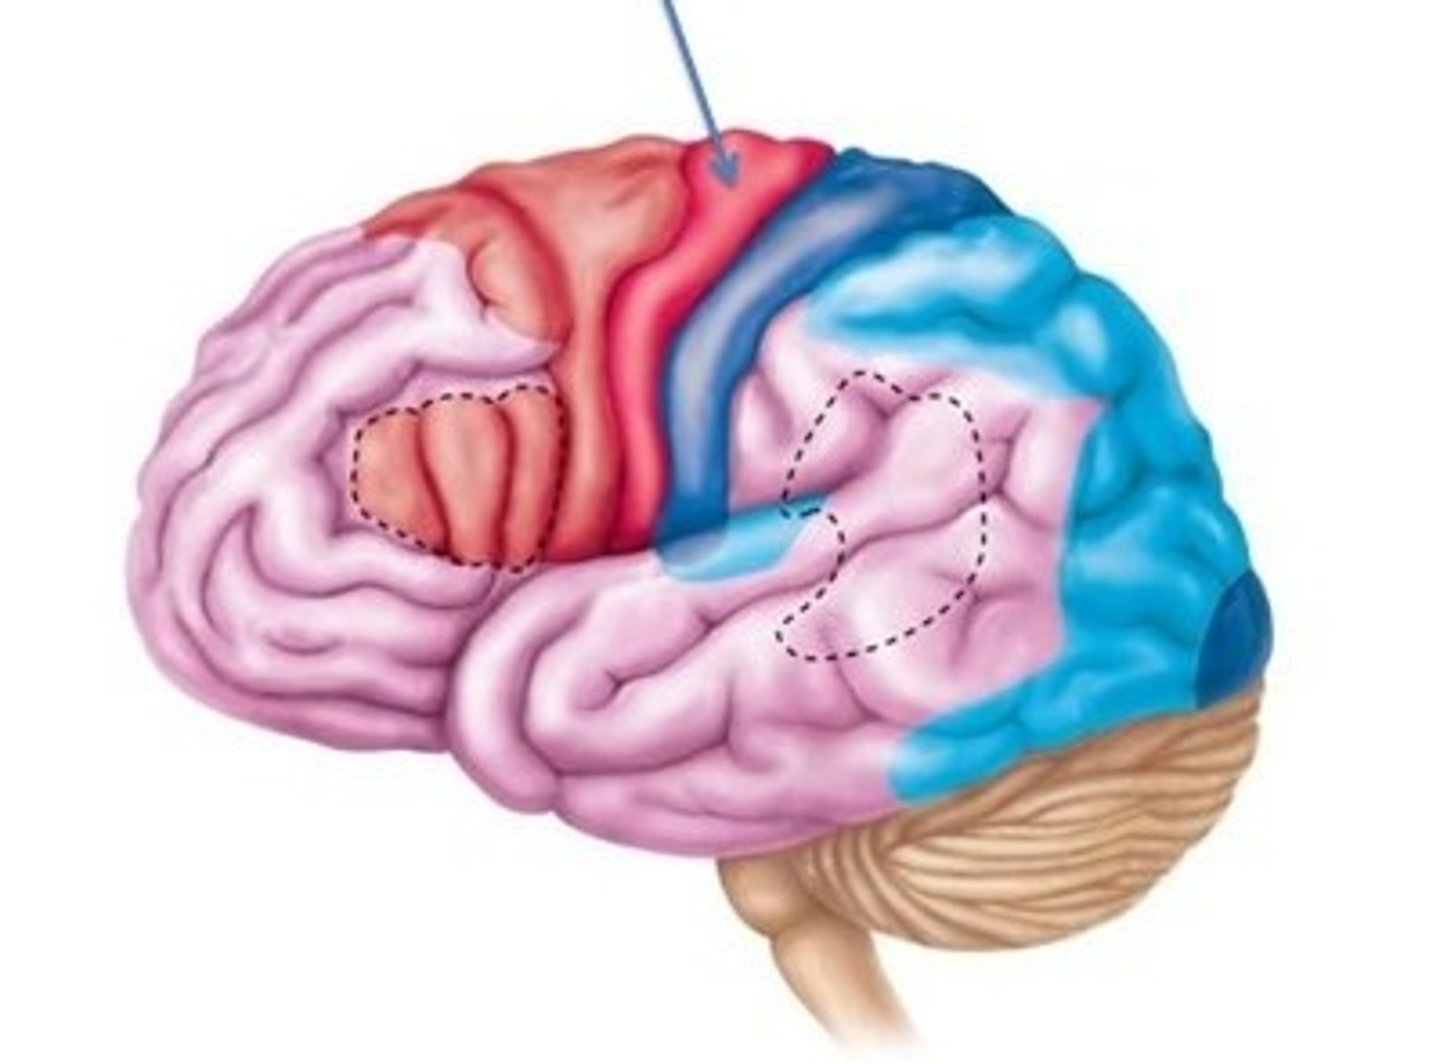

cerebral cortex

specific types of sensory, motor, & integrative signals are processed in certain regions of the cerebral cortex.

sensory areas of cerebral cortex

Primary somatosensory, Primary visual, Primary auditory, primary olfactory, primary gustatory

motor areas of cerebral cortex

voluntary muscle movements

primary motor cortex

located in the frontal lobe; is the key motor control center responsible for initiating and coordinating movements

premotor cortex

located immediately anterior to the primary motor cortex, responsible for movements such as typing

integrative areas of the cortex

higher cognitive functions; association areas, prefrontal cortex, wernickle's area, broca's area

association areas of cerebral cortex

integrate diverse information

prefrontal cortex

part of frontal lobe responsible for thinking, planning, and language

Wernickle's area

language comprehension

broca's area

speech production